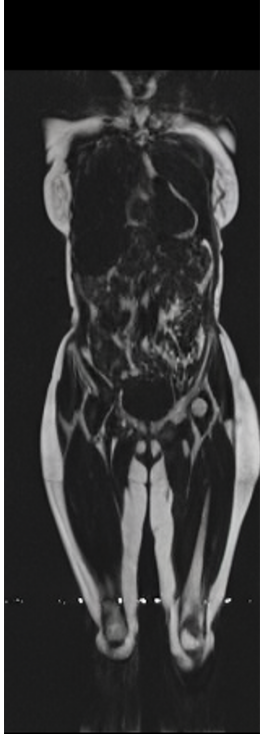

Our results unequivocally highlight the superior performance of X-Diffusion in terms of both qualitative and quantitative metrics. Representative MRI volumes generated by our pipeline, when juxtaposed with ground-truth images, showcased remarkable similarity, with even intricate physiological features like tumor information, spine curvature, and fat distribution being accurately captured.

Notably, X-Diffusion achieves state-of-the-art dB for a few input slices while baselines require more than 60 input slices to achieve similar performance (Figure 7). The margin is more than 12 dB PSNR for the 1-slice input in both the BRATS and the UK Biobank benchmarks (see Table 1 and Figure 6). For reference, two randomly sampled MRIs from UK Biobank would have a PSNR of 15.95 dB 0.36 (on 4800 randomly sampled examples). Omitting the preprocessing step of alignment DXA to MRI, leads to a drop of PSNR on average by 2.87 dB (29.01 dB 26.14 dB). The slices from 3D reconstructed volumes at varying depths and axis of rotation, visually match the ground truths for both brain and whole-body scans (see Figures 4 and 5 left). We also plot the error map (Figure 3) and the spread of the error (Figure 5 right) of such X-Diffusion generations to highlight the differences with the ground truth MRIs.

Preservation of Spine Curvature. For the spine segmentation on UK Biobank, we use a UNet++ model [83] with Dice Loss. We use a model trained to predict curves on DXA on UK Biobank [11]). We measure the Pearson correlation factor [11] of spine curvature measured on the generated MRIs where the input is a single MRI coronal slice, a single sagittal slice, or from the paired DXA, against the curvature of reference real MRIs of the same samples. The correlation coefficients are 0.89 for the coronal MRIs, 0.88 for the sagittal MRIs, and 0.87 for the DXAs on the test set of 308 human-annotated angles. We can then bin the curvature of the spines under different scoliosis categories based on human-annotated angles: mild: , moderate: , and severe . We show the results in Figure 8. This illustrates that the generated MRIs preserve the spine curvature from normal to severe scoliosis cases. Additional details about spine curvature are provided in supplementary material.

B.4 Preservation of Spine Curvature and Fat

For the spine segmentation on UK Biobank, we use a UNet++ model [83] with Dice Loss. We use a model trained to predict curves on DXA on UK Biobank [11]. We show in Figure IX that generated MRIs preserve the spine curvature from normal to severe scoliosis cases. We also study the case when DXA is used to generate the MRIs and show in Figure IX how the correlation to real curvatures compares to the input MRI case. The curvatures of the MRI generated from the coronal plane match the DXA curvatures more than the curvatures generated from sagittal MRI. This is expected since the antero-posterior plane of DXA is equivalent to the coronal plane for MRIs. This also explains the greater Pearson’s correlation coefficient of the coronal MRI (0.89) and DXA-generated curvature (0.88) compared to sagittal-generated curvature (0.87) relative to the reference curvature on the coronal plane. We observe though that MRI generation using X-Diffusion from another plane than the conventional plane for scoliosis assessment is valid.